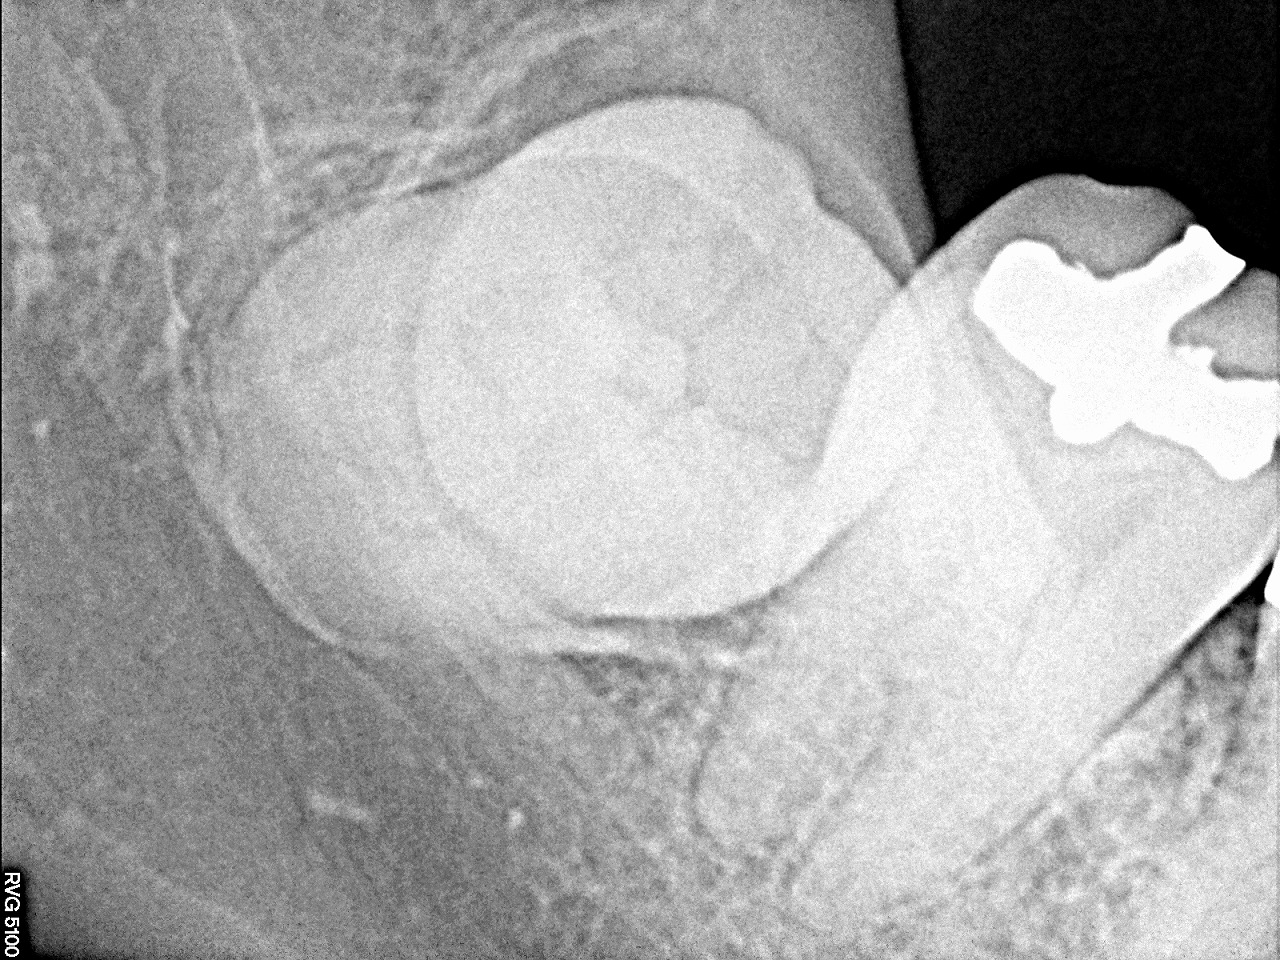

ここに親不知が埋伏しています

レントゲンになります

根尖部がわかりにくいのでもう1枚

このように埋伏していました